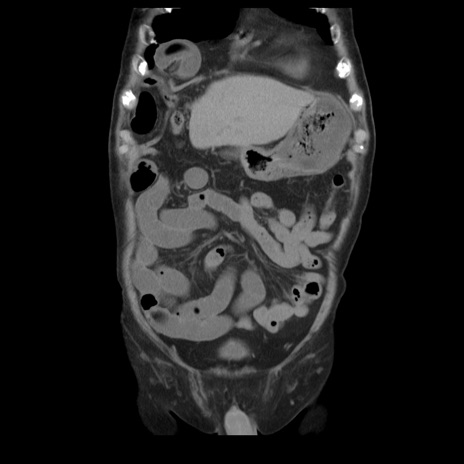

症例21(冠状断像)

【症例】70歳代男性

【主訴】腹痛

【現病歴】肝硬変・肝細胞癌にてかかりつけの方。約9時間前に食後より腹痛出現。症状が徐々に増悪し、嘔吐出現したため来院。

【既往歴】肝硬変、肝細胞癌(RFA、TACE後)

【身体所見】意識清明、表情苦悶様、BT 36℃、BP 129/78mmHg、P 88bpm、SpO2 97%(RA)、右上腹部から心窩部にかけて圧痛あり、反跳痛なし、筋性防御あり。

【データ】WBC 5800、CRP 0.16